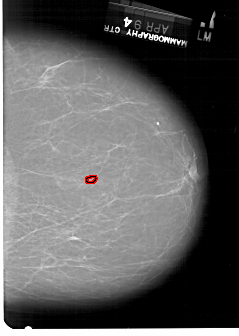

A_1331_1.LEFT_MLO

LEFT_MLO LINES 6871 PIXELS_PER_LINE 4231 BITS_PER_PIXEL 12 RESOLUTION 43.5 NON_OVERLAY

FILE: A_1331_1.RIGHT_MLO.OVERLAY

TOTAL_ABNORMALITIES 1

ABNORMALITY 1

LESION_TYPE CALCIFICATION TYPE PLEOMORPHIC DISTRIBUTION CLUSTERED

ASSESSMENT 4

SUBTLETY 1

PATHOLOGY BENIGN

TOTAL_OUTLINES 1

BOUNDARY